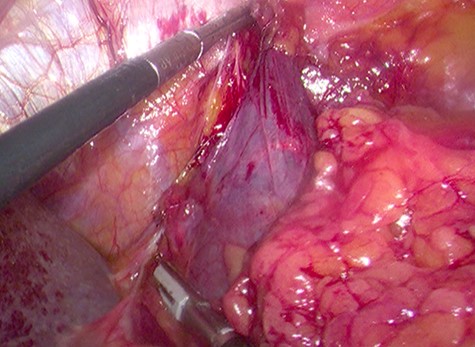

Because of its relatively large size and the patient’s request, he underwent a laparoscopic transperitoneal left adrenalectomy in the right lateral decubitus position (two 10-mm and one 5-mm ports). Intraoperatively, an enlarged left adrenal gland and a cystic lesion closely adherent to it were found, surrounded by adipose tissue (Figs 3 and 4). They were completely resected en bloc and removed in the endobag. No adverse events occurred postoperatively and he was discharged on Day 3.

Laparoscopic view of the retroperitoneal space containing the left adrenal gland and a cystic lesion surrounded by large amounts of adipose tissue.

Laparoscopic en bloc resection of the retroperitoneal cystic lesion adherent to the left adrenal gland and adipose tissue.